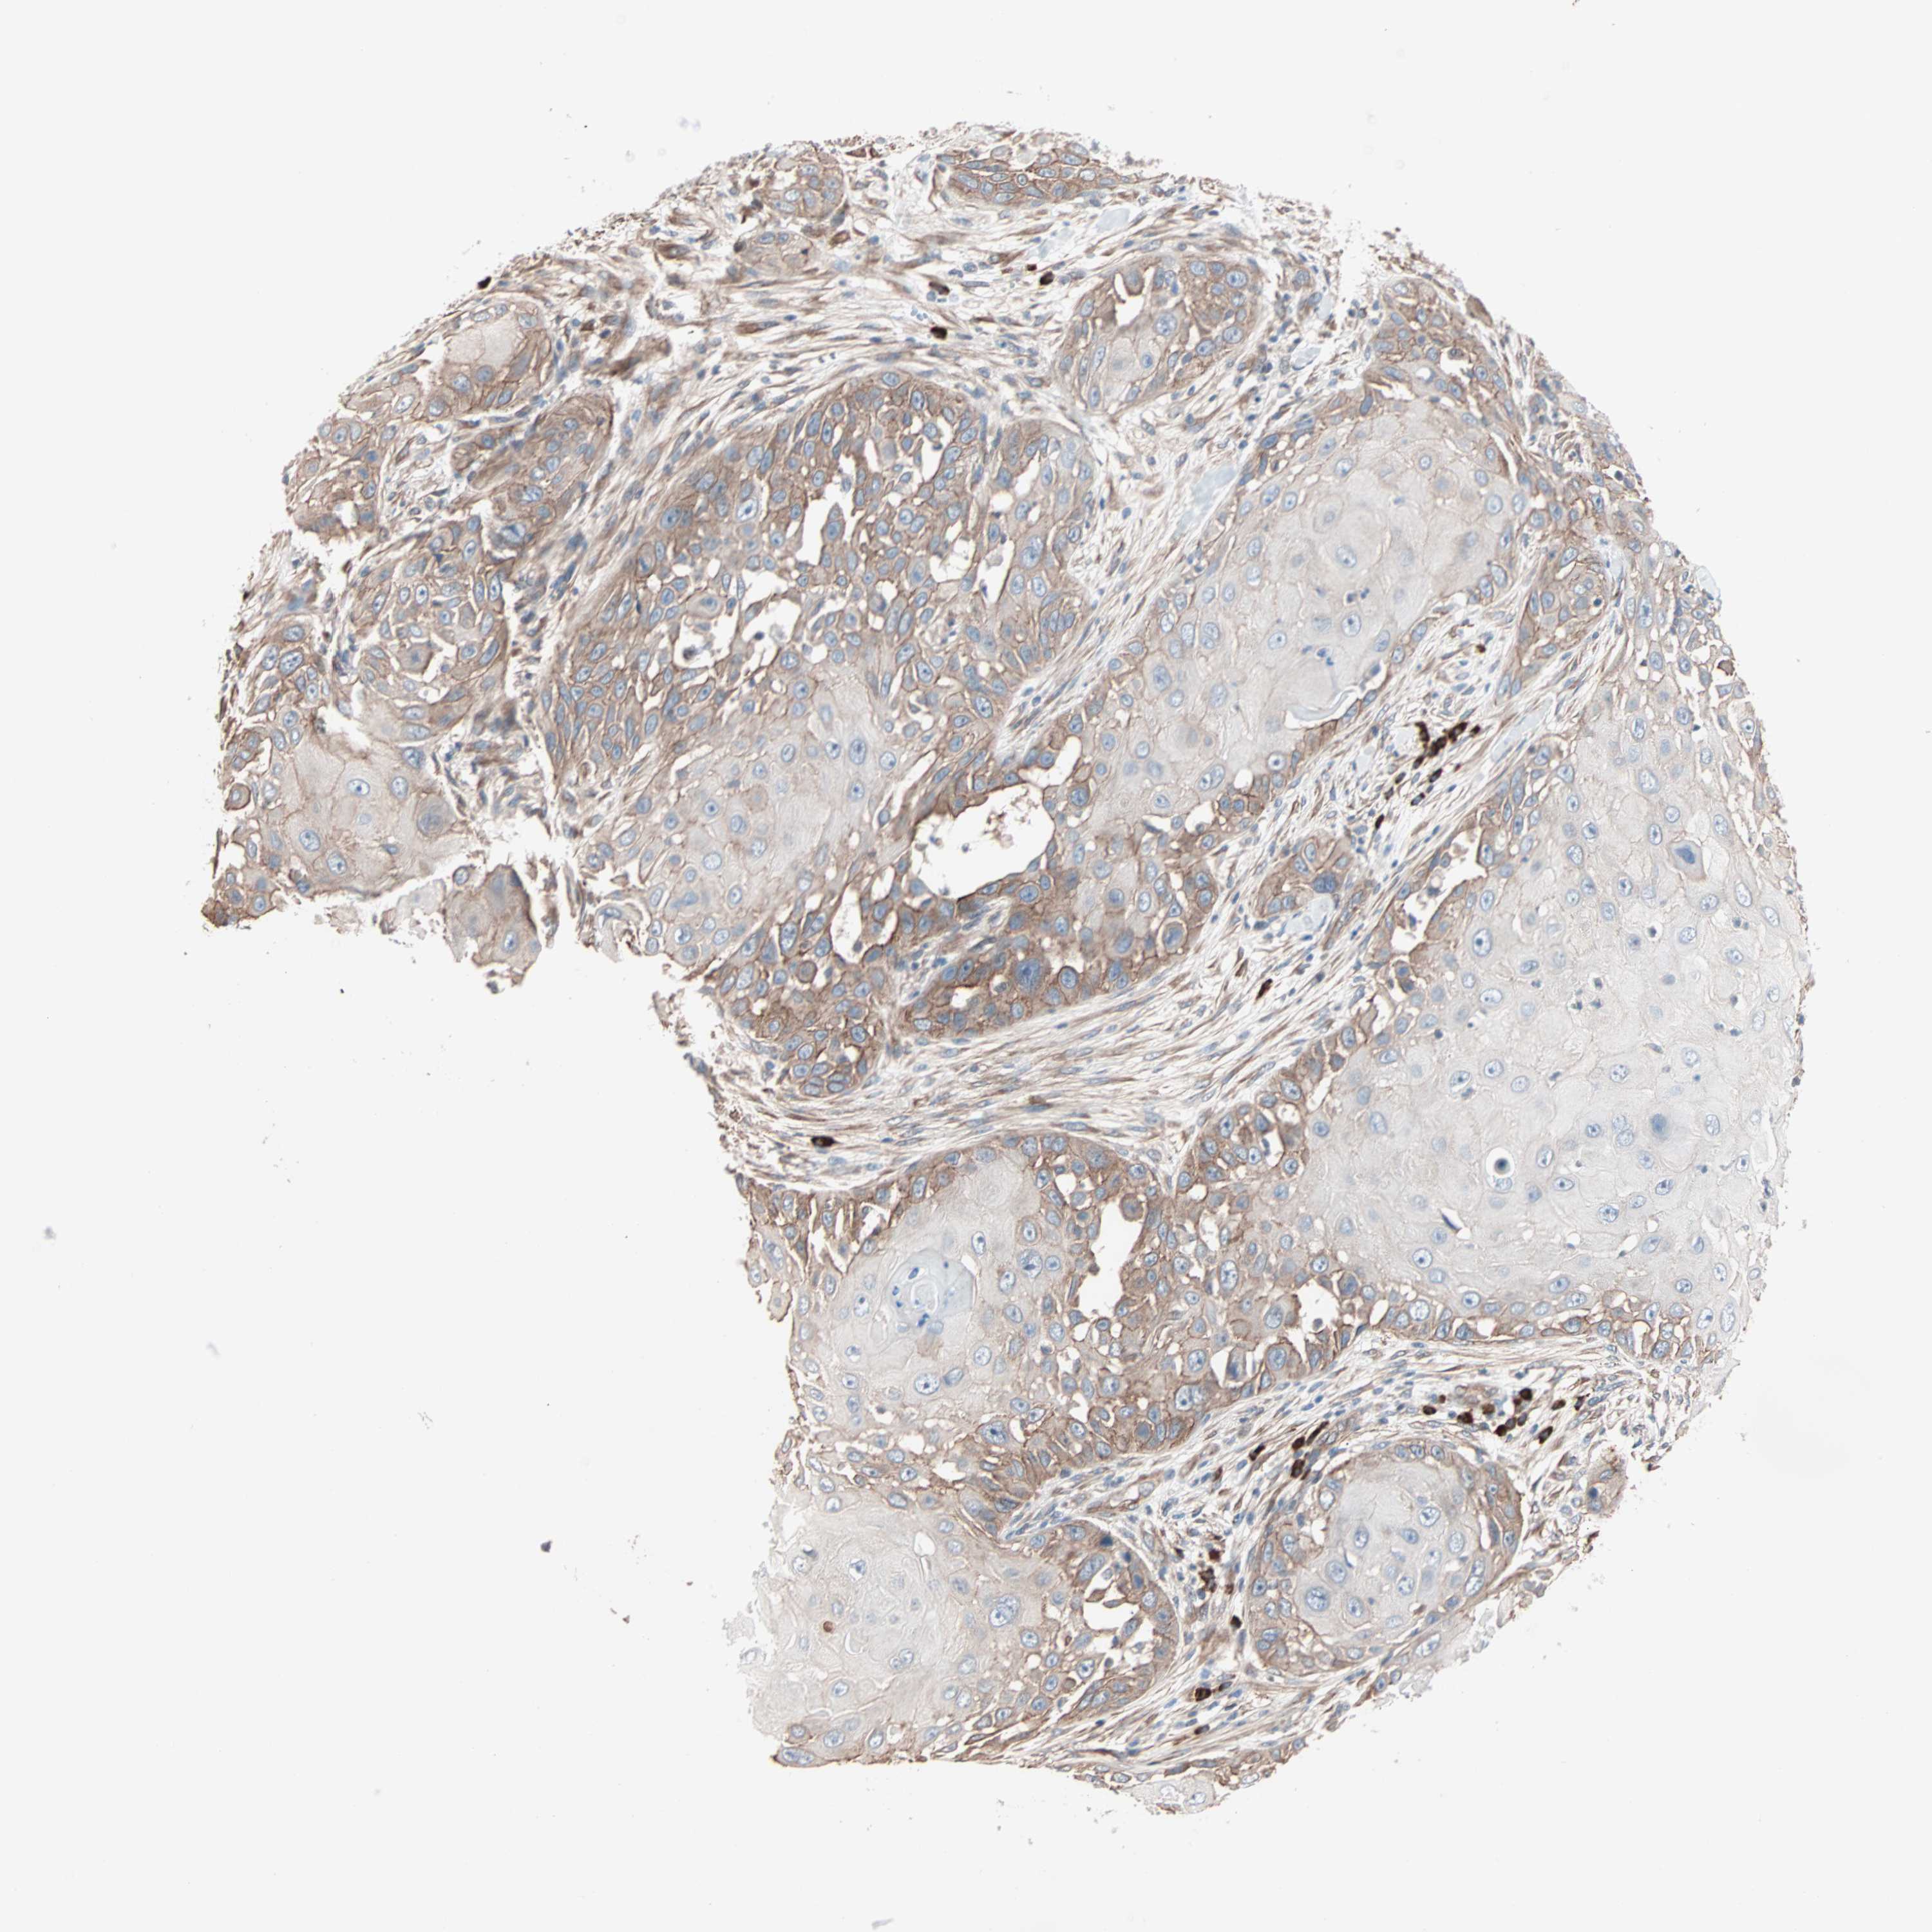

SKIN CANCER - Protein expressioni

A mouse-over function shows sample information and annotation data. Click on an image to view it in a full screen mode. Samples can be filtered based on level of antibody staining by selecting one or several of the following categories: high, medium, low and not detected. The assay and annotation is described here.

Each image is clickable and will lead to virtual microscopy that enables deeper exploration of all samples and also displays staining intensity scores, fraction scores and subcellular localization as well as patient and tissue information for each sample.

Antibody HPA007989

Staining

High

Strong

Quantity

Location

Squamous cell carcinoma, NOS